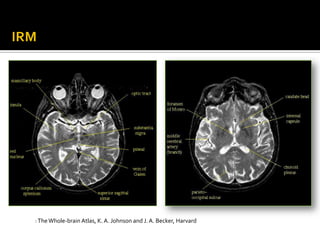

: The Whole-brain Atlas, K. A. Johnson and J. A. Becker, Harvard

…Contd : The Whole-brain Atlas, K. A. Johnson and J. A. Becker, Harvard